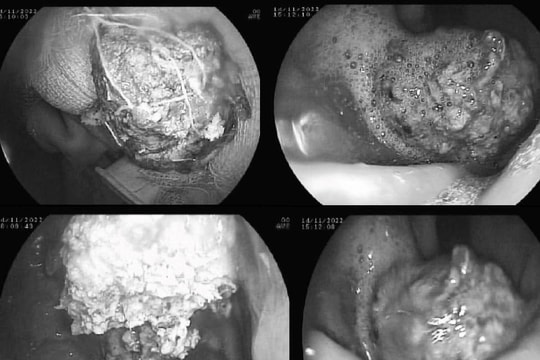

Tại bệnh viện, qua nội soi dạ dày, các bác sĩ phát hiện bệnh nhân co một khối bã thức ăn với kích thước khoảng 4x4 cm nằm trong dạ dày.

GĐXH – Tại bệnh viện, các bác sĩ phát hiện bệnh nhân có khối dị vật là bã thức ăn màu vàng đặc quánh, đen đặc lòng thân vị dạ dày gây hạn chế lưu thông.

PLBĐ - Người phụ nữ 57 tuổi nhập viện do đau tức thượng vị, đầy và nóng bụng…Nội soi phát hiện bã thức ăn lớn trong dạ dày.